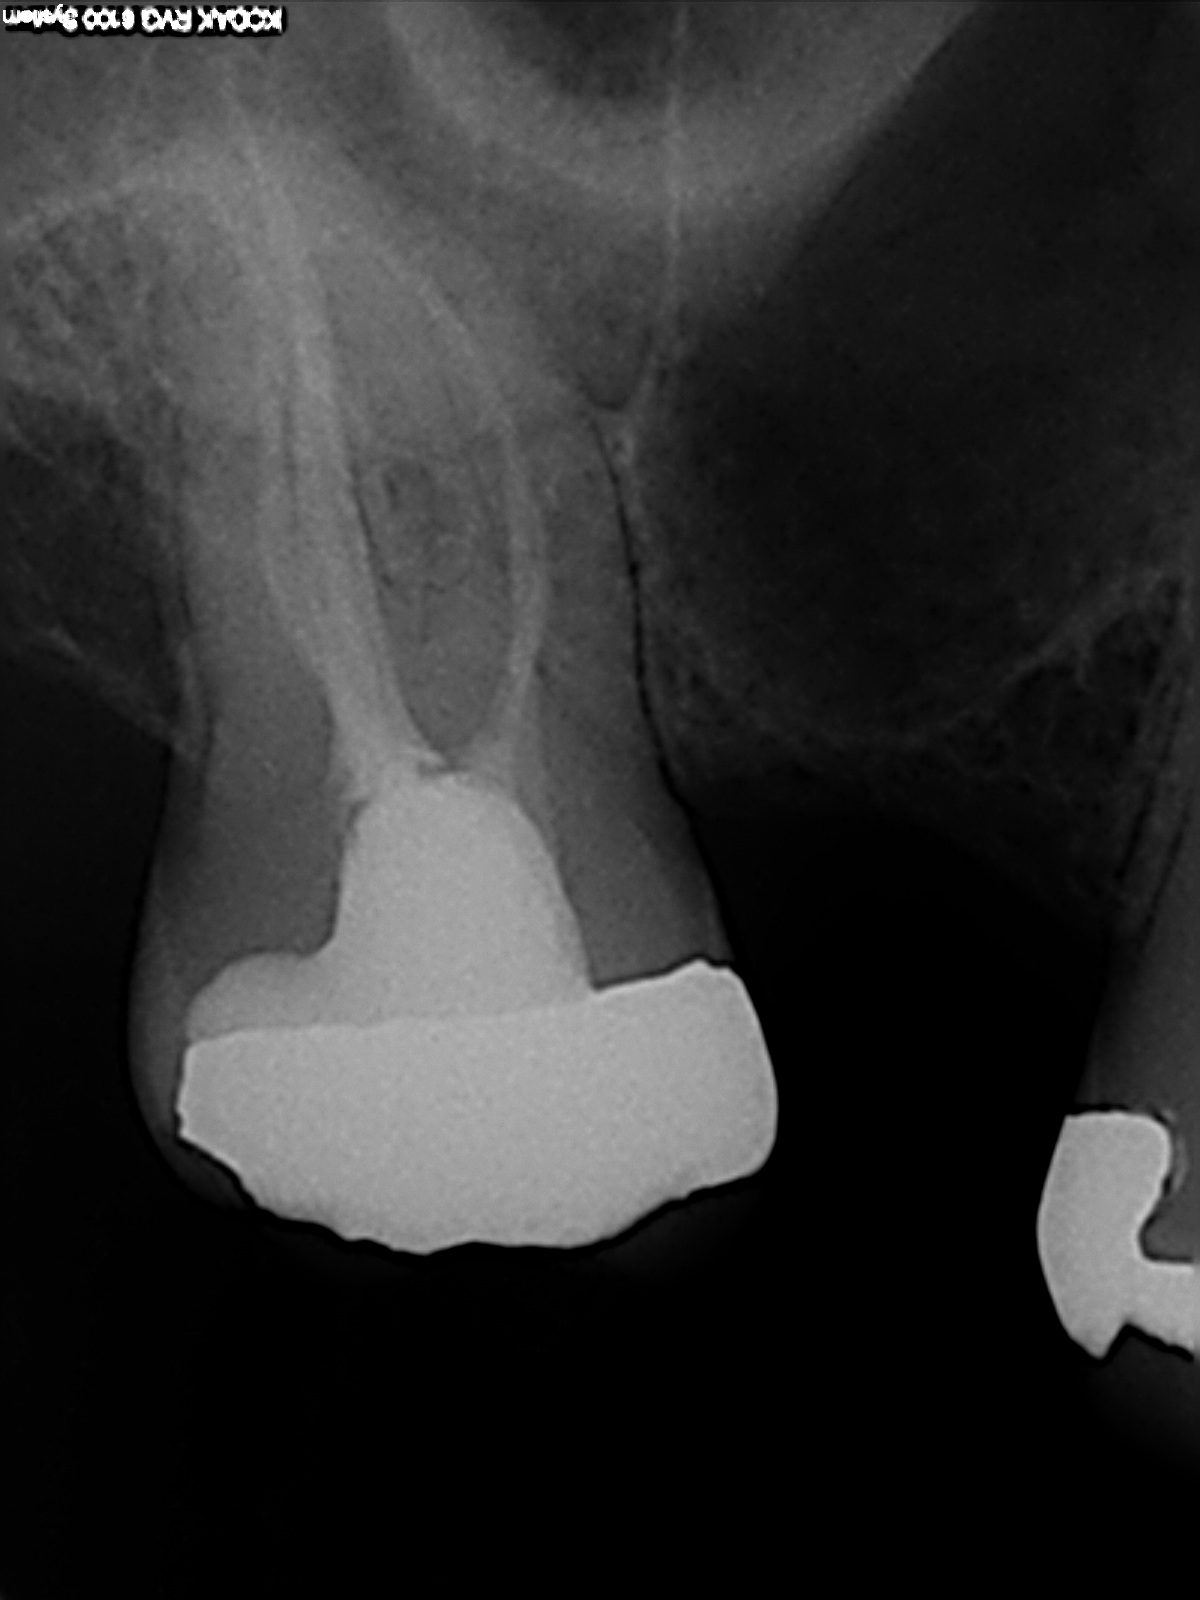

Zahnfilm 17

ZE Planung